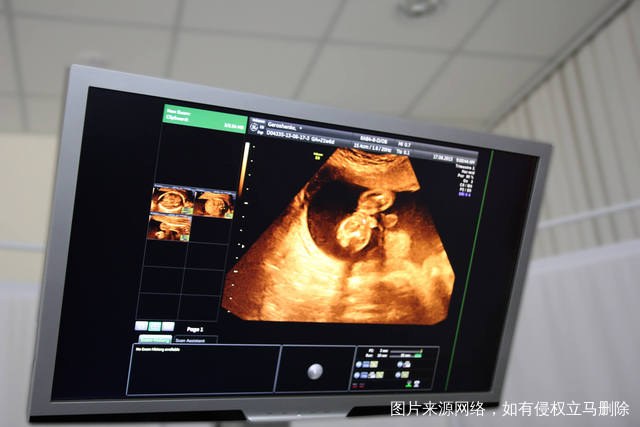

如果要做试管婴儿的话,相信大家基本上也都希望能够选择一个技术最好的医院,试管婴儿哪家医院好?

试管婴儿哪家医院好?通过以上的一些介绍,大家可以了解一下现在的这些试管婴儿技术可做的医院,其实从现有的情况来看,我们在选择医院的时候,可根据自己所在的地区来进行选择。